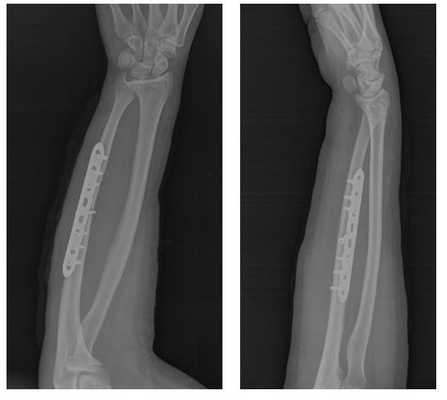

Клинический пример хирургического лечения перелома локтевой кости.

Пациент П. 39 лет, получил перелом локтевой кости в результате прямой травмы (падение на бордюрный камень с упором на согнутую в локтевом суставе руку).

Обратился в РТП, была наложена гипсовая повязка, лечился консервативно.

Обратился на консультацию в К+31. С целью ранней реабилитации, активизации, профилактики замедленной консолидации и формирования ложного сустава, полного восстанволения функции конечности предложено оперативное лечение - открытая репозиция, остеосинтез перелома пластиной и винтами Synthes.

Пациент госпитализирован с приёма, проведено полное предоперационное обследование, операция выполнена в день обращения.

На рентгенограммах после операции остеосинтез выглядит так.